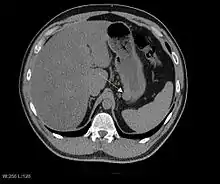

Радиологические исследования используются для уточнения локализации новообразования, выявления признаков инвазии и метастазирования. Проявления ГИСО варьируют в зависимости от размера опухоли и поражённого органа. Диаметр опухоли может составлять от нескольких миллиметров до более 30 см. Крупные опухоли обычно вызывают клинические проявления, бессимптомные опухоли обычно небольших размеров и имеют лучший прогноз.[3][16] Большие опухоли чаще ведут себя более злокачественно, однако и небольшие ГИСО могут иметь агрессивное течение.[17]

Так как ГИСО происходят из мышечного слоя (который располагается глубже слизистого и подслизистого слоёв), небольшие ГИСО чаще визуализируются как подслизистое или внутристеночное объёмное образование. При исследовании желудочно-кишечного тракта с барием обычно выявляются ровные контуры образования, формирующие прямой или тупой угол со стенкой, что наблюдается и при любых других интрамуральных процессах. Поверхность слизистой интактна, за исключением случаев изъязвления, которые присутствуют при 50 % ГИСО. При КТ с контрастным усилением, небольшие ГИСО обычно визуализируются как интрамуральные образования с ровными, чёткими контурами и гомогенным контрастированием.

По мере роста опухоли, она может проецироваться снаружи от органа (экзофитный рост) и/или в просвете органа (интралюминальный рост); чаще всего ГИСО растут экзофитно, таким образом большая часть опухоли располагается в проекции брюшной полости. Если увеличение объёма опухоли опережает рост её кровоснабжения, опухоль может некротизироваться в толще, с формированием центральной зоны жидкостной плотности и кавитацией, что может приводить к изъязвлению и формированию соустья с полостью органа. В этом случае исследование с бариевой взвесью может демонстрировать газ, уровни газ/жидкость или депонирование контрастного препарата в этих областях.[17][18] При КТ с контрастным усилением крупные ГИСО выглядят негомогенно, в связи с неоднородностью структуры опухоли, обусловленной участками некроза, кровоизлияниями и полостями, что радиологически проявляется контрастированием опухоли преимущественно по периферии.[16]

Злокачественность может проявляться локальной инвазией и метастазами, обычно в печень, сальник и брюшину. Однако встречаются случаи метастазирования в кости, плевру, лёгкие и забрюшинное пространство. По сравнению с аденокарциномой желудка или лимфомой желудка/тонкой кишки, злокачественная лимфаденопатия при ГИСО не типична (<10 %).[16] При отсутствии метастазов радиологическими признаками злокачественности являются большие размеры опухоли (>5 cm), гетерогенное контрастирование после введения контрастного препарата и наличие изъязвлений.[3][16][22] Также явно злокачественное поведение (без учёта опухолей со злокачественным потенциалом) реже наблюдается при ГИСО желудка, с отношением доброкачественных опухолей к явно злокачественным 3-5:1.[3] Даже в случае наличия радиологических признаков злокачественности, следует учитывать, что они могут быть обусловлены другой опухолью; окончательный диагноз должен быть установлен иммуногистохимическим методом.

Рентгенографические исследования с барием и компьютерная томография обычно применяются для обследования пациентов с абдоминальными жалобами. Исследования с барием выявляют патологические изменения в 80 % случаев ГИСО.[17] Однако некоторые ГИСО могут располагаться полностью вне просвета органа, что делает невозможным их выявление при исследовании с барием. Даже в случае выявления патологических изменений при рентгенографии с барием, необходимо последующее дообследование методами МРТ или КТ. КТ-исследование проводится с пероральным и внутривенным контрастным усилением, и позволяет визуализировать ГИСО в 87 % случаев[17] Мягкие ткани наиболее контрастны при МРТ, что помогает в выявлении интрамуральных образований. Для оценки васкуляризации опухоли необходимо внутривенное введение контрастного препарата.

Методами выбора в диагностике ГИСО являются КТ и МРТ,[23]:20–21 и, в некоторых случаях, эндоскопическое УЗИ. Томографические методы позволяют уточнить органную принадлежность опухоли (что может быть затруднительно при её больших размерах), визуализировать инвазию в соседние органы, асцит и метастазы.